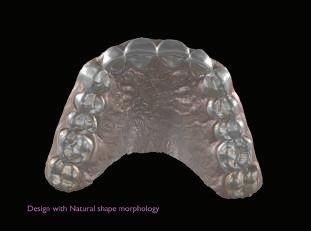

След диагностиката бяха направени екстра- и интраорални снимки, както и рентгенографии; професионалното почистване бе от изключителна важ ност, бяха дадени и инструкции за лич на орална хигиена. Бе направено интра орално сканиране с Medit i500. Цялата тази информация бе използ вана в приложението Smilecloud за 2D биометричен дизайн. В приложението са налични естест вени форми на зъбите и щом бяха под брани зъби и бе направен дизайн

библиотеката на Exocad. Струва си да се отбележи, че 2D дизайнът от Smile Cloud бе спазен до последния детайл в Exocad smile creator с цел да се създаде 3D obj файл със зъбните форми. След като естетичният дизайн бе готов в model creator модула на Exocad, адитивен 3D мок-ъп модел бе експорти ран и принтиран от принтер Formlabs 3. Моделът бе използван за направата на силиконов водач, за да се изготви мо тивационен мок-ъп в устата на паци ента и да се оценят естетичните па раметри. След като пациентът одобри вида на усмивката си, мок-ъпът бе използван за финализиране дизайна на усмивка та. Мок-ъпът бе използван също така като водач по време на мекотъканна та хирургия, както и при препарация на зъбите.

Препарираните зъби бяха импорти рани в Exocad и насложени върху ес тествените форми от биометричния дизайн, като така стана ясно дали зъ бите са били препарирани коректно. По този начин зъболекарят и зъботехни кът работят в една и съща екосистема и резултатът е оптимален. С короната се справихме чрез диги тална редукция на циркония в Exocad, като по този начин на практика създа дохме циркониево кепе, след което про изведохме фасета от IPS Empress Cad Multi. Кепето от Katana Zirconia на зъб 12 с букално послойно нанесена керами ка бе фрезовано (послойното нанасяне бе направено, за да се подобри връзката и да се осигури адхезивно циментиране на фасетата към циркониевото кепе, както и за да се напасне цветът към този на съседните зъби). При първото сканиране регистрирах ме цялата горна зъбна дъга, така че, ко гато се наложи да сканираме повторно, бе изтрит и сканиран наново само зъб 12, тъй като венците не бяха отдръп нати при второто сканиране.

рентгенографии. Инициална терапия и професионално почистване. Интраорално сканиране с цел диги тално планиране. Регистрация и 3D ориентиране на ок лузалната равнина на горна и долна челюст в пространството. 2D дигитално планиране и дизайн на усмивката посредством приложение то Smile Cloud. 3D дигитално планиране и дизайн на функционалните и естетичните па раметри. 3D дигитален дизайн и адитивен мокъп на горна челюст. 3D принтиране и мок-ъп модели. Мотивационен мок-ъп. Фини корекции за постигане на фи налния дизайн. Мекотъканна хирургия с мок-ъпа като водач Препарация през мок-ъпа, използвай ки дизайна като водач за финалната препарация в Exocad. Циркониево кепе ще бъде циментира но с цел адхезивно залепяне на фасе та на края. Кепето има същия цвят като този на съседните зъби, за да може фасетата да се впише перфект но в цялостната усмивка. Изработване на 12 IPS Empress Cad Multi фасети с послойно нанесена ке ТОТАЛНА РЕХАБИЛИТАЦИЯ НА УСМИВКАТА С ИЗЦЯЛО ДИГИТАЛЕН ПРОТОКОЛ Д-р Калин Маринов и зт. Стефан Петров рамика букално върху зъбните препа рации и върху първичното циркони ево кепе (има възможност за ецване и адхезивно

Една седмица след препарацията на зъбите и циментирането на цирко ниевото кепе бяха изработени 12 IPS Empress Cad Multi фасети. Макро- и микротекстурата на фасе тите бяха направени на ръка, след кое то бяха нанесени 3D характеризации с боички, а полирането отново бе напра вено ръчно, за да им се придаде естест вен и естетичен вид. Предизвикателството тук беше короната да има същите оптични характеристики като тези на остана лите зъби при естествена светлина, през поляризационен и флуоресцентен филтър. 3D принтерът бе Fromlabs, софтуерът за фрезоване – Mill Box, а фрез апаратът –imes icore CORiTEC 350i. В крайна сметка постигнахме ес тествен вид на усмивката с натурал на зъбна морфология при изцяло диги тален протокол, при който дизайнът бе направен първоначално и през всич ки етапи на лечението се придържахме към него до самия край Излишно е да отбелязваме, че всички сме удовлетворени от постигнатото! Преди След Победител в категория „Клиничен случай с изцяло дигитален протокол“ в конкурса „Усмивка на годината 2022“